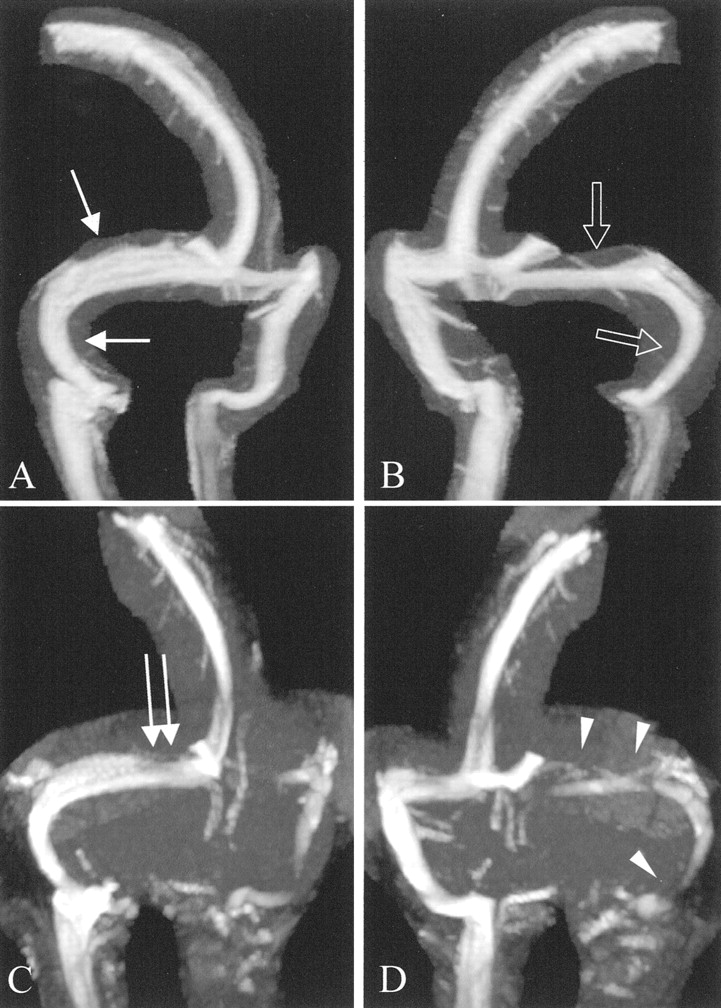

图1所示。Auto-triggered elliptic-centric-ordered控制病人的三维先生gadolinium-enhanced造影术。(一)横向和(B)前后的最大强度投影(MIPs)显示轮廓用来创建序列的分段MIPs获得每个控制和颅内高压症病人。(汉英)前后的左前斜(老挝),右前斜(RAO)分段MIPs。这三个选择拍摄的图像90张图片,电影圈的读者了。